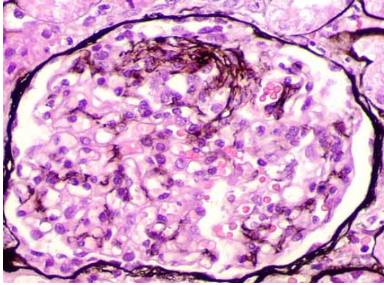

A

Nódulos Kinestil Willson

pass +